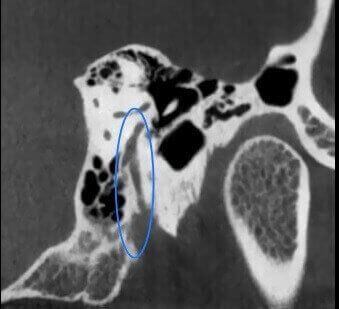

ATM Bocca Aperta